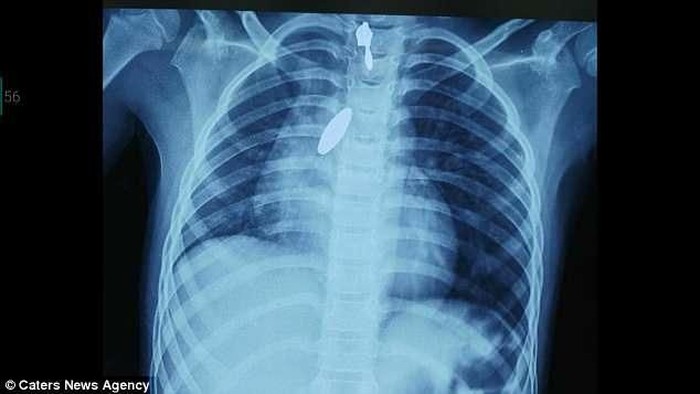

Jika tidak dikeluarkan, bisa membahayakan saluran napas. Foto: internet |

Magnet yang ada di paru-paru kanan perlahan ditarik menuju mulut menggunakan magnet lainnya. Selama proses berlangsung, jalur pernapasan pasien tetap dipantau untuk menghindari sesak napas.

Jika tidak dikeluarkan, bisa membahayakan saluran napas. Foto: internet